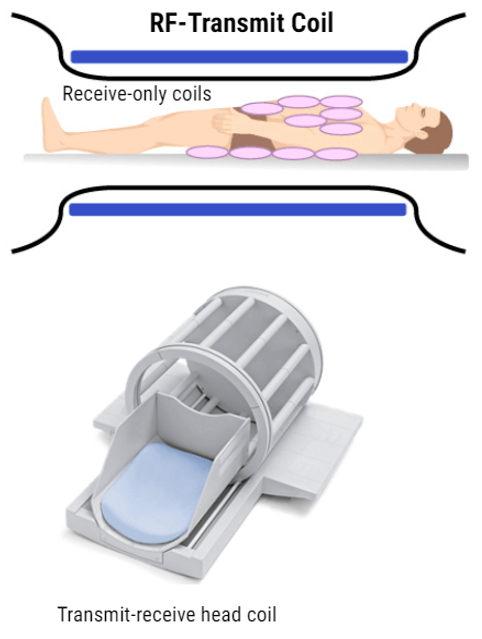

Data collection begins at the coil. Recall that the coil acts like an antenna that captures a radio wave. In our words, the coil is capturing the resonance wave or the echo.

MRI Coils

We now understand that during the process of MRI, the resonance in the form of an echo wave is given off during the relaxation of T1 and T2. In order to create the image, we need to collect that echo. In MRI we use very special equipment called Coils. The coil acts like an antenna so to speak, similar to the way an antenna on a car might pick up the radio waves being transmitted from radio stations.

There are several different types of coils, some are specifically designed for specific body parts, and some are capable of being used for any type of imaging. Also, a coil can be classified as a receive-only. What this means is the coil may ONLY receive the signal but does not transmit – for these types of coils, the transmission of the RF energy comes from the inherent body coil of the magnet.

A coil can also transmit and receive. A transmit/receive coils do both functions – transmission of RF and Receiving of the echo. These types of coils are also referred to as “local transmit coils” because of their proximity to the body part. The only thing we cannot have is a transmit-only coil. Even the TR body coil can transmit RF energy and Receive a signal.